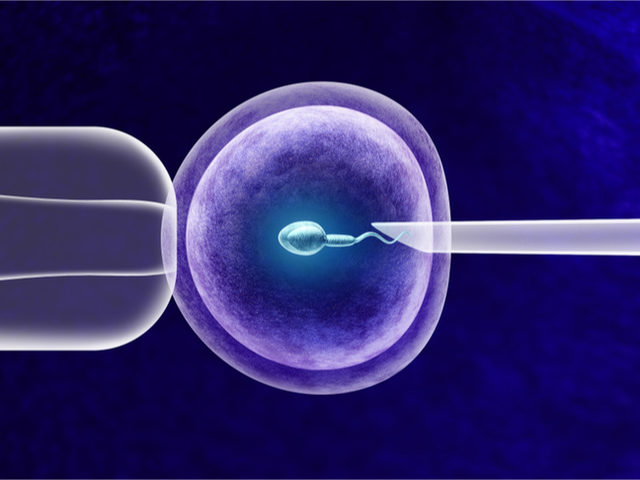

Canımlar adetime az kaldı 3. İğne ile yapılan uyarıda daha fazla yumurta elde edildiğinden ve hapların rahim iç tabakası üzerine potansiyel olumsuz etkilerinden dolayı daha yüksek gebelik. Gonal f ve menogon kullanıp hamile kalanlar var mı. Kadından yumurta toplama ile elde edilen yumurta ve erkekten alınan spermin laboratuvar ortamında birleştirilmesi döllenmesi sonrası elde edilen embriyonun rahim içine nakledilmesidir.